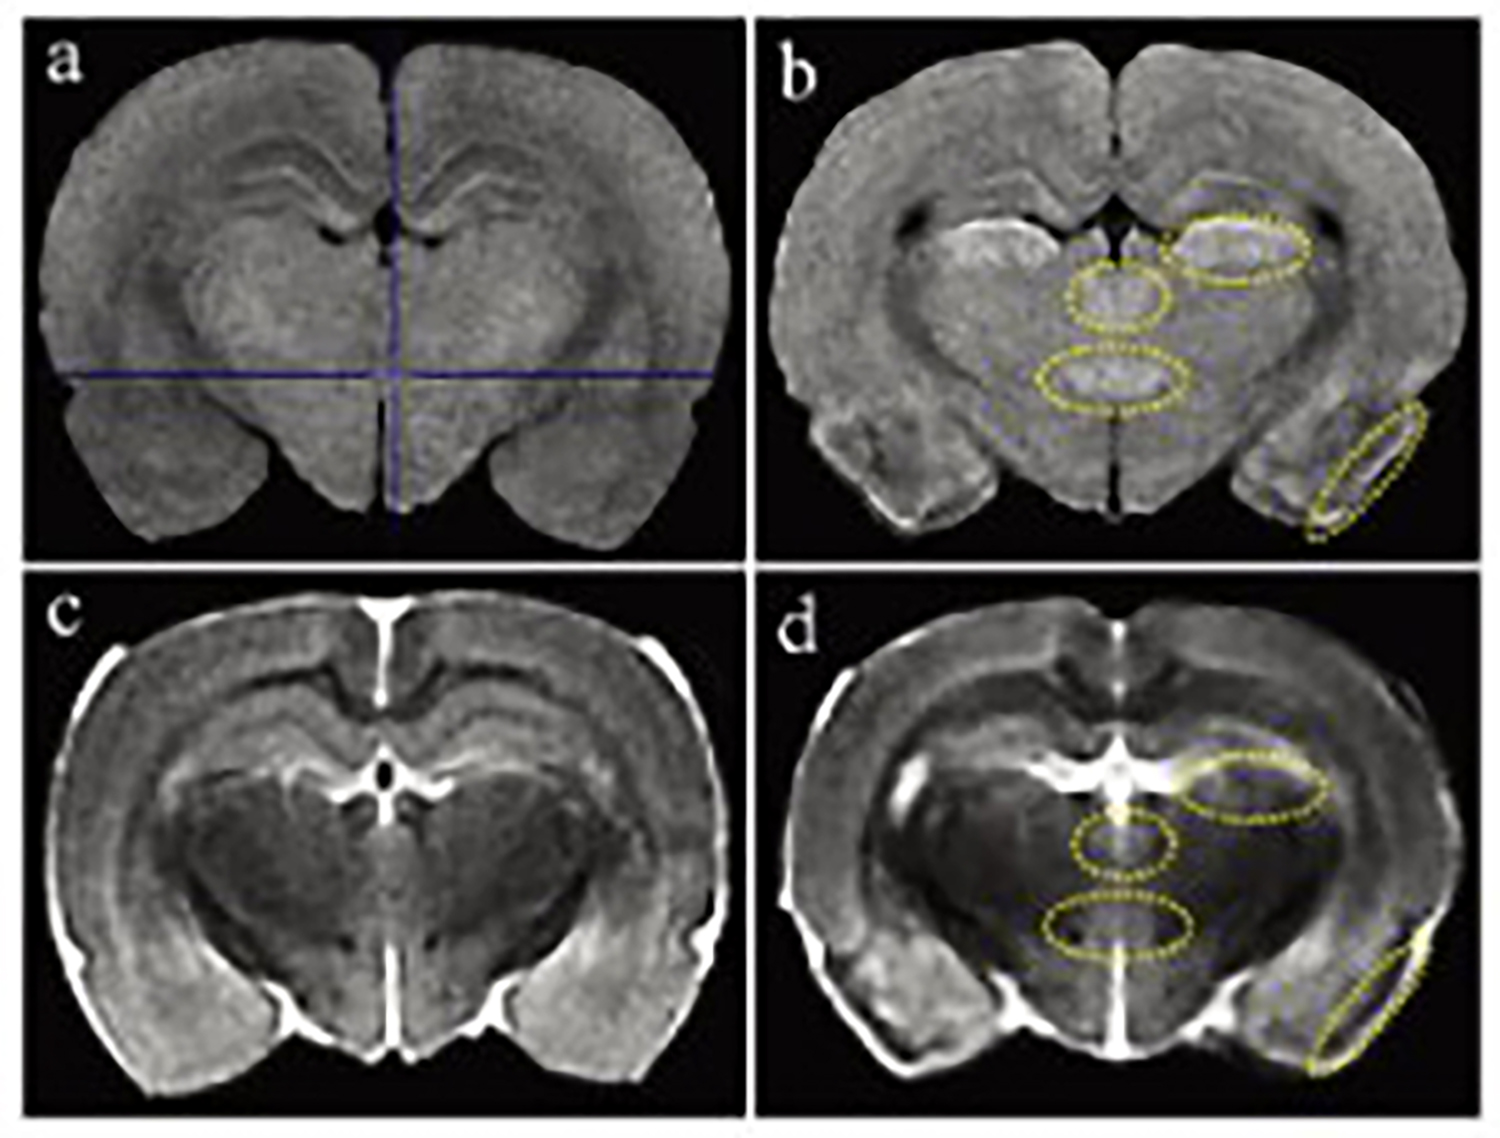

The Dixon fat suppression technique, originally proposed by Dixon, is based on the chemical shift difference between water and fat protons.By using different echo times, it acquires two sets of signals: one where water and fat protons are in phase, and another where they are opposed in phase.This enables the effective separation of water and fat signals in magnetic resonance imaging.